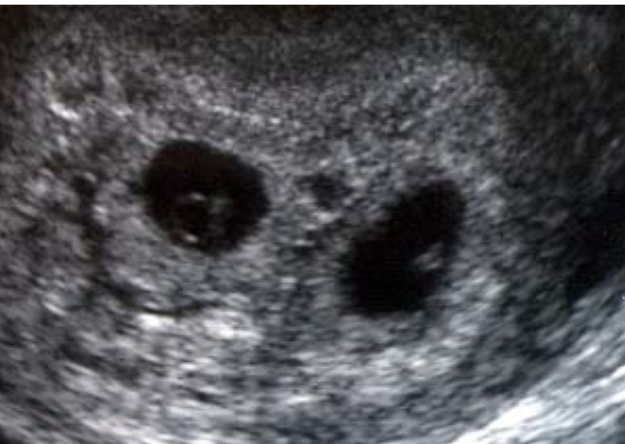

12

Q

A

diamniotic

monochorionic